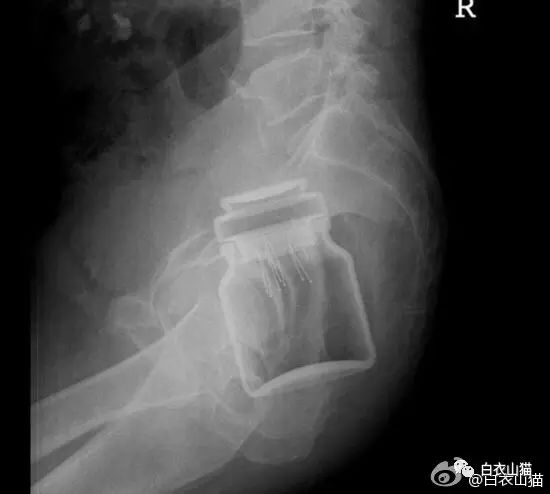

杯子。

这个还是比较常见的,认得出来吗?

男性病人,也是个杯子。

这个也是一个玻璃杯。